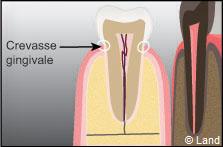

– sus-gingival, visible, d’origine salivaire de couleur blanche ou jaune, de consistance plus ou moins dure. Il est près de la limite gingivale et le plus souvent proche de la sortie des canaux excréteurs de la salive.

– sous gingival, invisible, d’origine sérique, de couleur marron foncé ou noir verdâtre, dense et dur, très adhérent. Il est situé dans le sillon gingivo-dentaire et dans les poches parodontales.